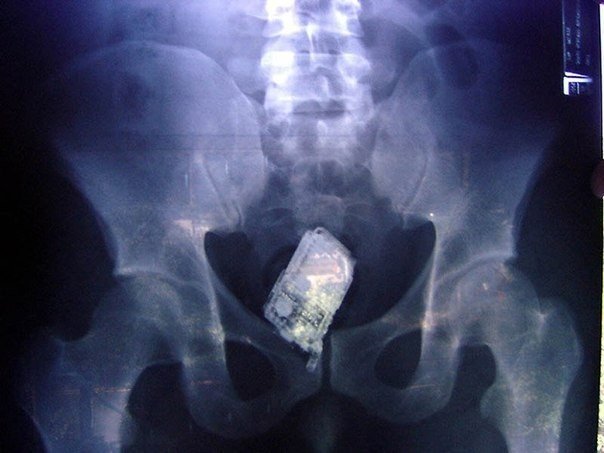

5) Un teléfono móvil en los intestinos de un prisionero